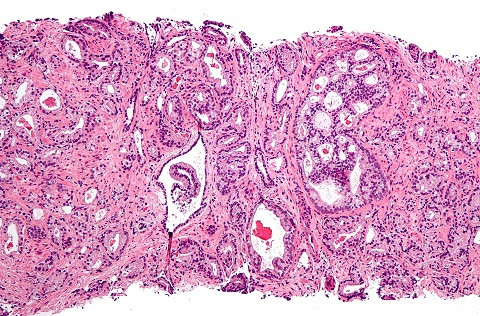

| Ung thư tiền liệt tuyến có thể do di truyền. |